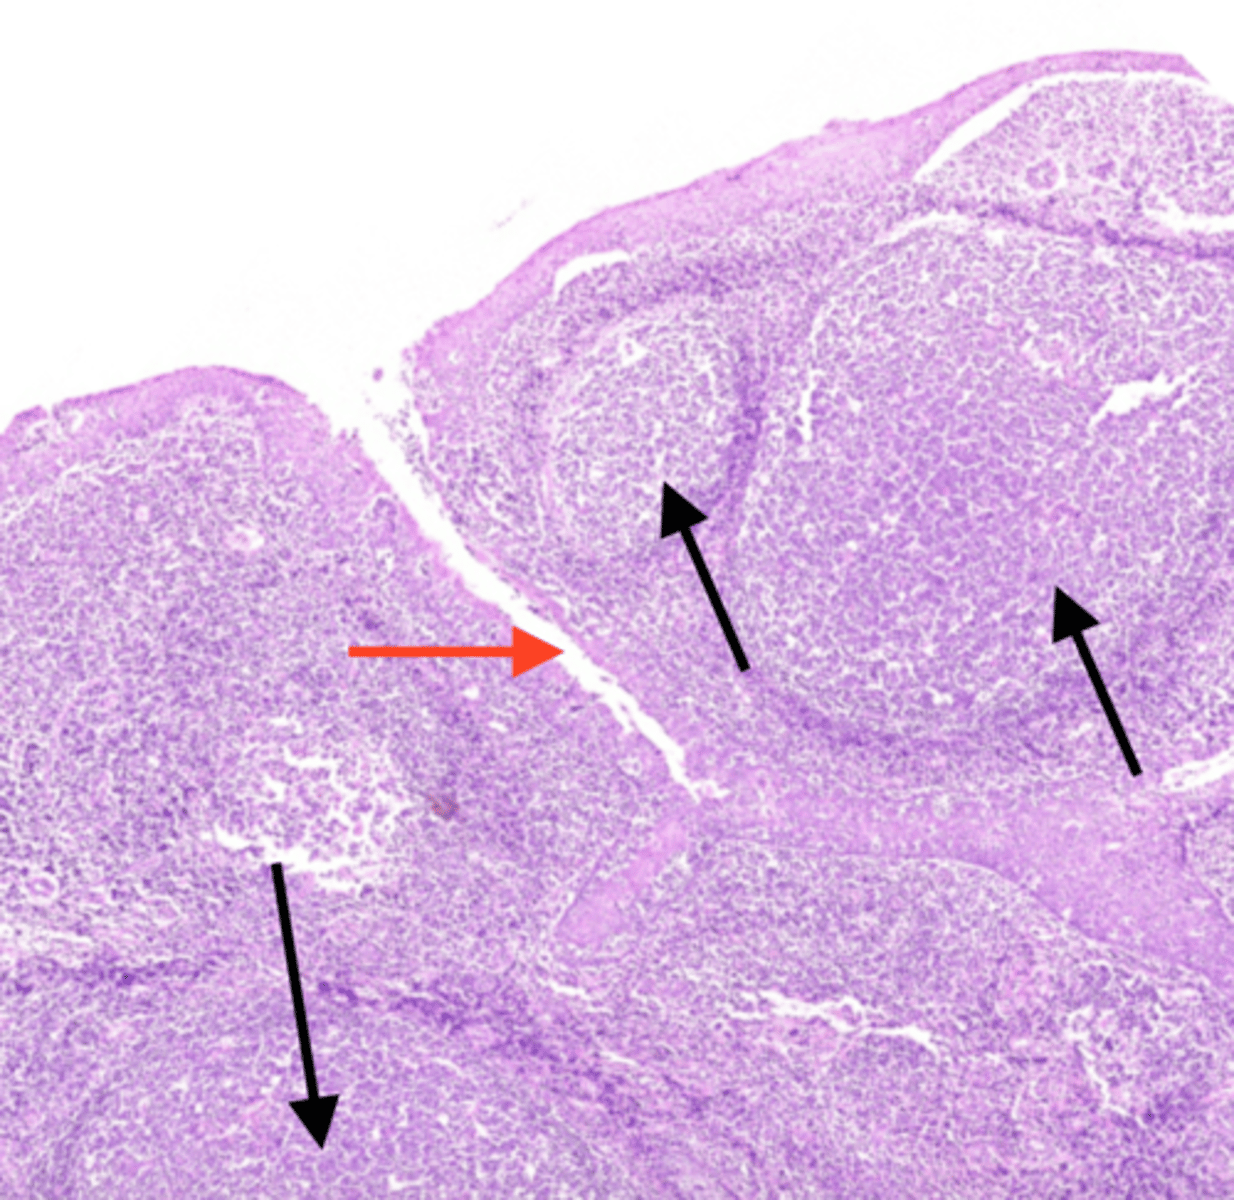

tonsillar crypts

contains lymphocytes and bacteria. Deep to the epithelium and adjacent to the crypts you can see dense lymphatic tissue

tonsillar capsule

made of dense connective tissue. It separates the tonsil from the subjacent tissues. Helps prevent the spread of infection.